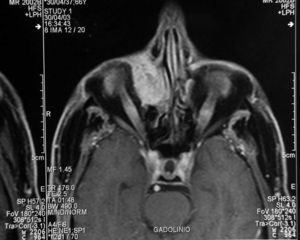

Se le realizó una TC orbitaria (figs. 1 y 2), sin administración de contraste intravenoso y se obtuvieron imágenes en los planos axial y coronal, con algoritmos de reconstrucción de partes blandas y de hueso. Se visualizaba la tumoración como una masa de partes blandas de densidad homogénea, morfología ovoidea, bordes bien definidos y contornos regulares, de 4 x 3 centímetros de diámetro anteroposterior y transversal respectivamente, localizada en el canto interno de la órbita derecha, que ocasionaba desplazamiento lateral del globo ocular y de la musculatura extrínseca ocular, con ensanchamiento del conducto lacrimonasal, que orientaba hacia un origen en el saco lacrimal. Se asociaba remodelación de las celdas etmoidales anteriores, sin evidenciarse signos de destrucción del hueso, ni afectación de estructuras vecinas.

Fig. 1.--Tomografía computarizada orbitaria, plano axial sin administración de contraste intravenoso. Se observa una masa de partes blandas bien definida, localizada en el canto interno de la órbita derecha, que produce el desplazamiento del globo ocular y musculatura extrínseca ocular y se asocia a ensanchamiento del conducto lacrimonasal.